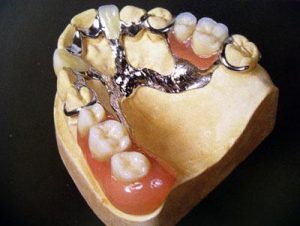

Что такое бюгельное протезирование?

Когда носить «бабушкины» пластмассовые протезы не хочется, условий для несъемного протезирования нет, а имплантология по тем или иным причинам недоступна, врачи могут предложить вам бюгельное протезирование. О данном протезе мало что известно среднестатистическому пациенту, хотя бюгельный протез является прекрасным вариантом протезирования для молодых пациентов. Итак, что такое бюгельный протез и когда он используется?

Бюгельное (от нем. Bugel - дуга) протезирование - одна из разновидностей съемного протезирования зубов, представляющая собой съемную ортопедическую конструкцию, нагрузка в которой распределяется не только на опорные зубы, но и на слизистую оболочку. В бюгельной конструкции используется легкая металлическая дуга, которая позволяет использовать для опоры не только десны, но и собственные зубы. У бюгельного протеза компактный вид, он достаточно удобен, долговечен и прочен.

Бюгельный протез состоит из:

1. металлического каркаса (который включает в себя: дугу (бюгель) и фиксирующие элементы);

2. седло видимая часть с искусственной десной, на которой располагаются искусственные зубы.

Наличие прочного металлического каркаса, дает возможность максимально уменьшить размеры протеза, а современные сплавы на основе титана позволяют делать бюгельные протезы практически невесомыми. Небольшие размеры и легкий вес является важным фактором в процессе привыкания к протезу. В большинстве клинических случаев пациент уже в первый день пользования бюгельным протезом не ощущает никаких неудобств.

Преимуществами бюгельного протезирования являются: наименьшая нагрузка на десны и распределение остальной нагрузки между здоровыми зубами; такие протезы не закрывают неба - поэтому привыкание к ним происходит быстрее; бюгельные протезы более эстетичные, прочные, долговечные, удобные в использовании, они не ломаются, так как в основе их прочный металлический каркас.

По креплению бюгельное протезирование делят на кламмерное (фиксируется на зубах с помощью дужки) и замковое.

У бюгельных зубныx протезов с замками крепление скрыто внутри зубного протеза, поэтому, в отличие от зубных протезов с кламмерами, снаружи не видно, что во рту есть съёмный зубной протез.

Вместо массивного, закрывающего почти всю челюсть, пластмассового базиса обычного зубного протеза у бюгельных протезов ажурное тонкое литьё, к тому же существует огромное количество вариантов конструкций, которые учитывают все индивидуальные особенности пациента.

Благодаря использованию новых материалов и оборудования стало возможным сделать конструкцию бюгельного зубного протеза лёгкой, удобной и не заметной для посторонних глаз. Пациенты пользуются такими зубными протезами с удовольствием.

К тому же, как это не странно звучит, но бюгельные съемные протезы имеют ряд преимуществ даже перед несъемными протезами:

1) Бюгельные протезы в большинстве случаев не требуют препарирования (обтачивания) зубов и изготовления коронок на опорные зубы, поэтому они менее травматичны для твердых тканей зубов, пульпы и периодонта.

2) Принцип съемности обеспечивает возможность легко извлечь протез для осуществления гигиенического ухода. Материалы, использующиеся для их изготовления, легко очищаются обычной водопроводной водой, а собственные зубы эффективно очищаются зубной щеткой с пастой. Такая эффективность гигиенического ухода за полостью рта и протезом невозможна при несъемном протезировании, т.к. между десной и искусственными зубами образуются ниши, в которых скапливаются остатки пищи, откладывается зубной камень, обильно развивается микрофлора.

3) Большой ассортимент искусственных зубов дает возможность изготавливать съемные протезы по цвету, форме и размеру точно соответствующие естественным зубам. К тому же, искусственные зубы в съемных протезах фабричного изготовления, заведомо прочнее искусственных зубов лабораторного изготовления в несъемных зубных протезах.

3) Большой ассортимент искусственных зубов дает возможность изготавливать съемные протезы по цвету, форме и размеру точно соответствующие естественным зубам. К тому же, искусственные зубы в съемных протезах фабричного изготовления, заведомо прочнее искусственных зубов лабораторного изготовления в несъемных зубных протезах.

Современные бюгельные протезы представляют собой высокотехнологичные конструкции, решающие сразу две задачи: шинирование зубов и протезирование, что очень важно для пациентов, страдающих заболеваниями парадонта (парадонтит, парадонтоз).

Уход за бюгельными протезами довольно прост. Необходимо утром и вечером очищать протез. На ночь бюгельный протез можно не снимать, что, конечно, психологически очень комфортно.

Бюгельное протезирование является на сегодняшний день самым эффективным видом протезирования, если сравнивать его с другими видами съемных протезов. Эффективность выражается как в удобстве ношения бюгельного протеза и удобстве приема пищи, так и надежности, долгом сроке службы. Однако, обо всем по порядку…

Отличия бюгельных протезов от протезов из пластмассы:

Бюгельные протезы применяются для съемного протезирования при частичной потере зубов. Главное отличие этого типа протезов от традиционных протезов из акриловой пластмассы заключается в наличии у них литого металлического каркаса, на который уже фиксируют искусственные зубы и базис из пластмассы. За счет наличия такого каркаса у бюгельных протезов удается значительно снизить толщину и объем пластмассового базиса, на который фиксируются искусственные зубы.

На рис. показано, насколько отличаются традиционные протезы из акриловой пластмассы – от бюгельных протезов. Особенно эти отличия ощутимы в области передних зубов, где у бюгельного протеза нет этой массивной перемычки, а имеется только тонкая металлическая дуга.